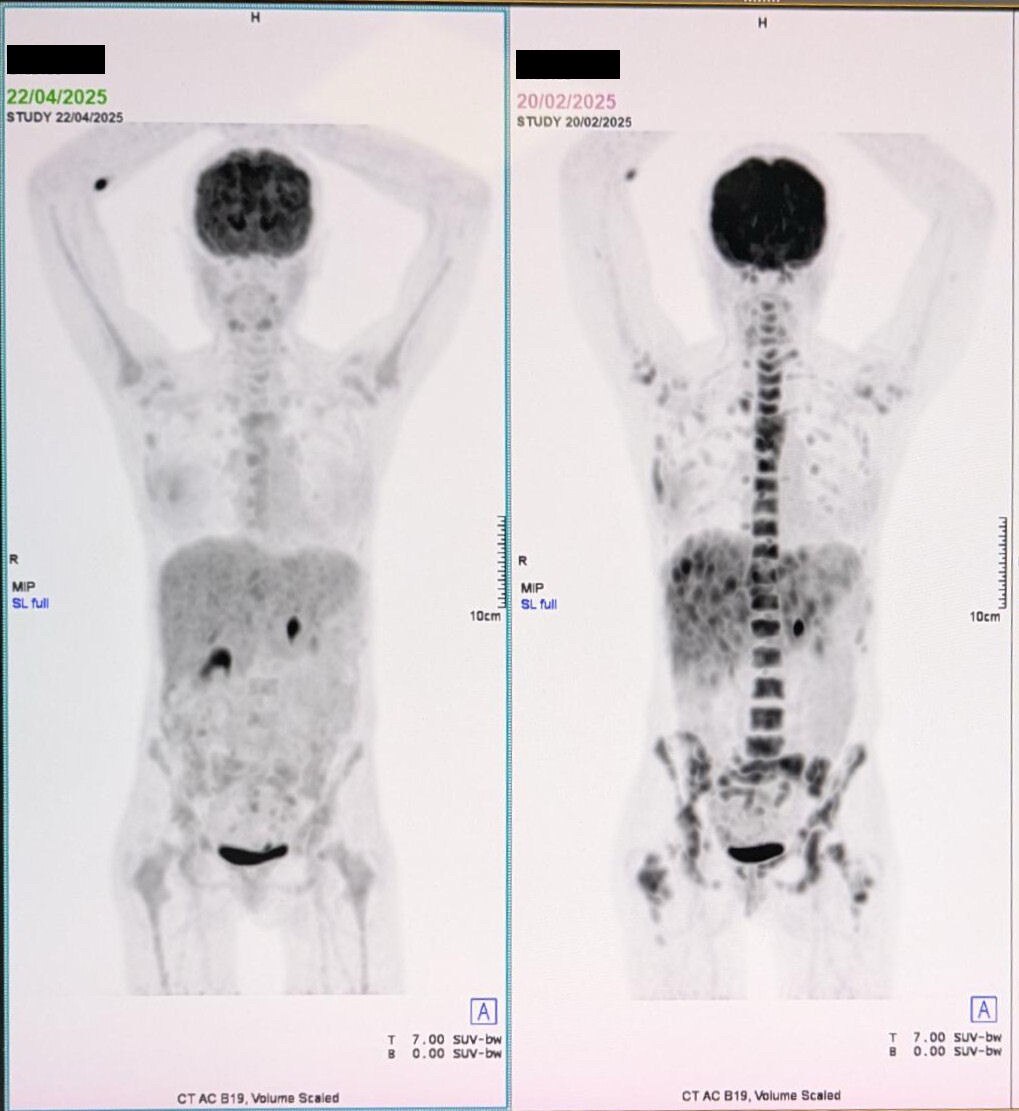

🔥抗癌奇迹!49岁澳洲女性战胜4期乳腺癌! 🩷 一位49岁的澳大利亚女性,确诊4期乳腺癌,癌细胞已转移至骨骼、淋巴和肝脏,情况危急。😔 但她没有放弃!从2025年2月中旬开始,她每天坚持使...

一位49岁的澳大利亚女性,确诊4期乳腺癌,癌细胞已转移至骨骼、淋巴和肝脏,情况危急。😔 但她没有放弃!从2025年2月中旬开始,她每天坚持使...